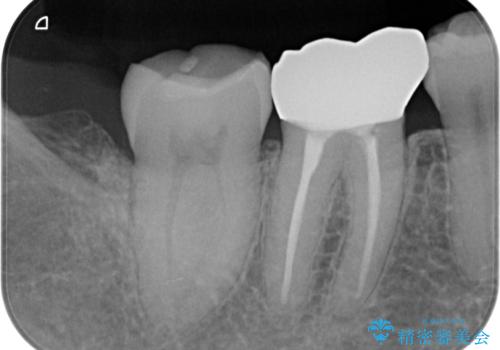

- 冷たいもので長引く痛みがあることを主訴に来院されました。

抜髄を行い、オールセラミッククラウンにて修復を行いました。

根管充填はバイオセラミックシーラーを使用しています。